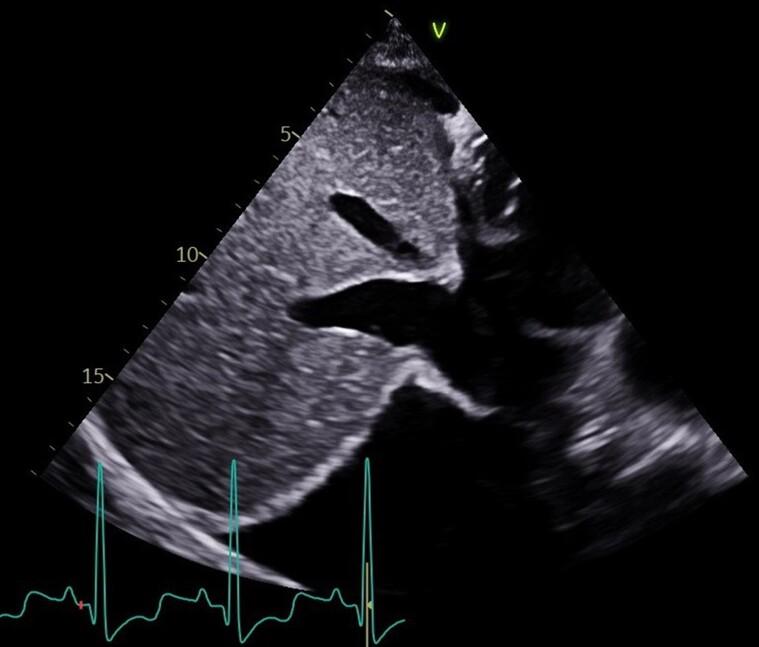

急性心力衰竭中的膈肌超声与膈肌二维斑点追踪成像:病例系列

Diaphragm ultrasound and diaphragmatic 2D speckle tracking imaging in acute heart failure: a case series.

Respiratory muscle function can be affected in patients with heart failure. Ultrasound can be used to assess diaphragm, the main inspiratory muscle. Speckle tracking imaging is an imaging technology providing the evaluation of tissue deformation during contraction. We aimed to evaluate the contribution of traditional echography and 2D speckle tracking imaging in the evaluation and monitoring of patients with acute heart failure (AHF).

CASE SUMMARY

We report a series of four cases of AHF. Diaphragm ultrasound coupled with diaphragm 2D speckle tracking imaging was performed at admission and after decongestive therapy, in cardiac intensive care unit. Patients, at admission, disclosed higher diaphragm 2D strain value and higher diaphragm inspiratory motion value in the context of higher cardiac loading that significantly decrease after decongestive therapy, except for one patient. Diaphragm motion remained less than 10 mm (weakness), despite medical therapy in Cases 2, 3, and 4. Among them, 3 months later, one patient (Case 3) experienced an episode of AHF.

心力衰竭患者的呼吸肌功能可能会受到影响。超声可用于评估主要吸气肌膈肌。斑点追踪成像技术是一种可在组织收缩时评估其变形情况的成像技术。我们旨在评估传统超声心动图和二维斑点追踪成像在急性心力衰竭(AHF)患者评估和监测中的作用。

病例总结

我们报告了4例AHF病例。在心脏重症监护病房,入院时和进行充血性心力衰竭治疗后均进行了膈肌超声检查及膈肌二维斑点追踪成像。患者入院时,在心脏负荷较高的情况下,膈肌二维应变值和膈肌吸气运动值较高,除1例患者外,充血性心力衰竭治疗后这些值显著降低。在病例2、3和4中,尽管进行了药物治疗,但膈肌运动仍小于10毫米(无力)。其中,3个月后,1例患者(病例3)发生了一次AHF发作。